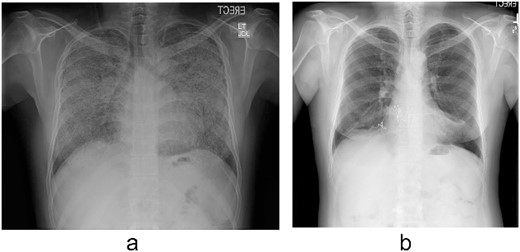

A 43-year-old Middle Eastern male, former smoker referred to our institute with chronic respiratory failure due to PAM for 5–6 years and oxygen dependence for 2 years and was listed for LTx. On investigations, patient had severe PH and moderate to severe right ventricle (RV) dilation and moderate RV dysfunction. His family history was negative for PAM. Pulmonary function test demonstrated forced expiratory volume in the first second (FEV1) 53%, forced vital capacity (FVC) 47%, total lung capacity (TLC) 47%, and diffusing capacity of the lungs for carbon monoxide (DLCO) 22% of predicted. His chest X-ray (Fig. 1a) was consistent with PAM. A donor became available, and patient underwent bilateral sequential LTx through clam-shell incision on veno-arterial extracorporeal membrane oxygenation (VA-ECMO) in September 2018 (Fig. 1b). Explanted lungs demonstrated anthracotic pleural surface with diffuse fibrous adhesions. Upon sectioning, lung parenchyma showed diffuse fibrosis and bilateral diffuse calcifications. Histopathology was also consistent with PAM. His postoperative course was complicated by primary graft dysfunction requiring VA-ECMO support for 2 days, prolonged mechanical ventilation with tracheostomy, right hemidiaphragm paralysis managed conservatively, and right femoral vein thrombosis requiring inferior vena cava filter insertion. Patient was discharged on post-operative Day 30 after decannulating the tracheostomy. Post-discharge, patient did well without any features of rejection on biopsy. Patient could not follow-up from January 2020 till June 2021 due to travel restrictions and had relatively poor compliance with immunosuppression due to unavailability. Patient had one episode of COVID-19 infection in April 2021 requiring hospitalization and had uneventful recovery. In June 2021, patient presented to our institute with worsening dyspnea and was diagnosed with CLAD with bronchiolitis obliterans syndrome and restrictive allograft syndrome without acute lung rejection (grade 0) and C4d immunostaining. However, donor specific antibodies were positive for HLADQ7 with mean fluorescence intensity (MFI) >5000. Pulmonary function test demonstrated FEV1 42%, FVC 53%, TLC 62%, and DLCO 40% of predicted. The patient was treated with intravenous immunoglobulin and underwent five cycles of plasmapheresis. Repeat donor specific antibody MFI reduced to below 5000 and lung biopsies remained negative for acute or chronic rejection. There was no change in FEV1 and FVC. There was no recurrence of calcification in the transplanted lungs. Patient was discharged with home oxygen therapy and maintenance intravenous immunoglobulin monthly for 6 months. In December 2021, patent again developed COVID-19 pneumonia that worsened, and patient was managed with mechanical ventilation and anti-viral medications. However, patient succumbed to death in January 2022 due to sepsis and multi-organ failure 28 days after hospitalization.

(a) Chest radiograph shows extensive calcification all over both lungs’ fields. (b) Chest radiograph after the transplant.